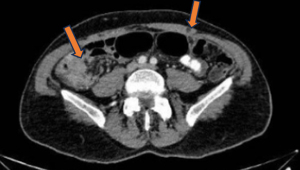

CT chest revealed no evidence of thoracic metastatic disease. Staging workup at that time revealed no evidence of extra-peritoneal disease. Repeat diagnostic laparoscopy a week later to evaluate for cytoreductive surgery revealed diffuse intraperitoneal disease with majority of small bowel and small bowel mesentery involved with cancer. The patient was deemed a nonsurgical candidate and referred to MD Anderson for opinion regarding further management. Repeat CT imaging one month later showed increasing peritoneal carcinomatosis (Figure 3). The patient was recommended palliative systemic chemo-immunotherapy on protocol 2022-0982 (phase 2 randomized trial of neoadjuvant or palliative chemotherapy with or without immunotherapy for peritoneal mesothelioma) and was randomized to Arm 1 with carboplatin + pemetrexed + bevacizumab + atezolizumab (9).